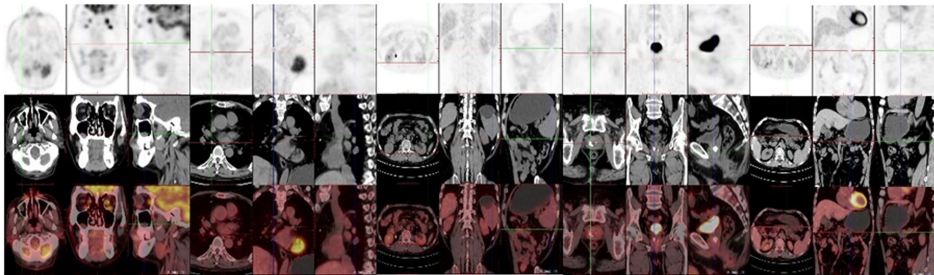

南京某医院团队在《The Egyptian Journal of Internal Medicine》报道了一例典型病例:一位59岁男性患者历经7年辗转求医,曾被误诊为成人Still病、ANCA(抗中性粒细胞胞浆抗体)相关性血管炎等疾病。该患者每次发作时出现特征性无瘙痒皮疹,1小时后体温飙升至39℃以上,伴随肌痛和关节痛,激素治疗仅能暂时缓解。研究团队通过系统的实验室检查排除了感染和肿瘤,发现其存在IgM κ型M蛋白阳性(4.17%)、持续升高的炎症指标(CRP 21.4 mg/L,ESR 64 mm/h),PET-CT和骨髓活检排除了淋巴增殖性疾病,最终符合Strasbourg诊断标准。

研究采用多学科交叉验证方法:通过免疫固定电泳检测M蛋白,PET-CT全身扫描排查肿瘤,骨髓流式细胞术分析克隆性增殖,并尝试IL-6受体拮抗剂托珠单抗治疗。当患者出现药物过敏后,调整为JAK抑制剂托法替布联合小剂量激素的过渡方案,同时等待IL-1受体拮抗剂(阿那白滞素)的应用。

患者皮疹呈现粉红色斑丘疹,主要分布于四肢和躯干,与典型荨麻疹不同之处在于无瘙痒且抗组胺药无效。影像学显示: